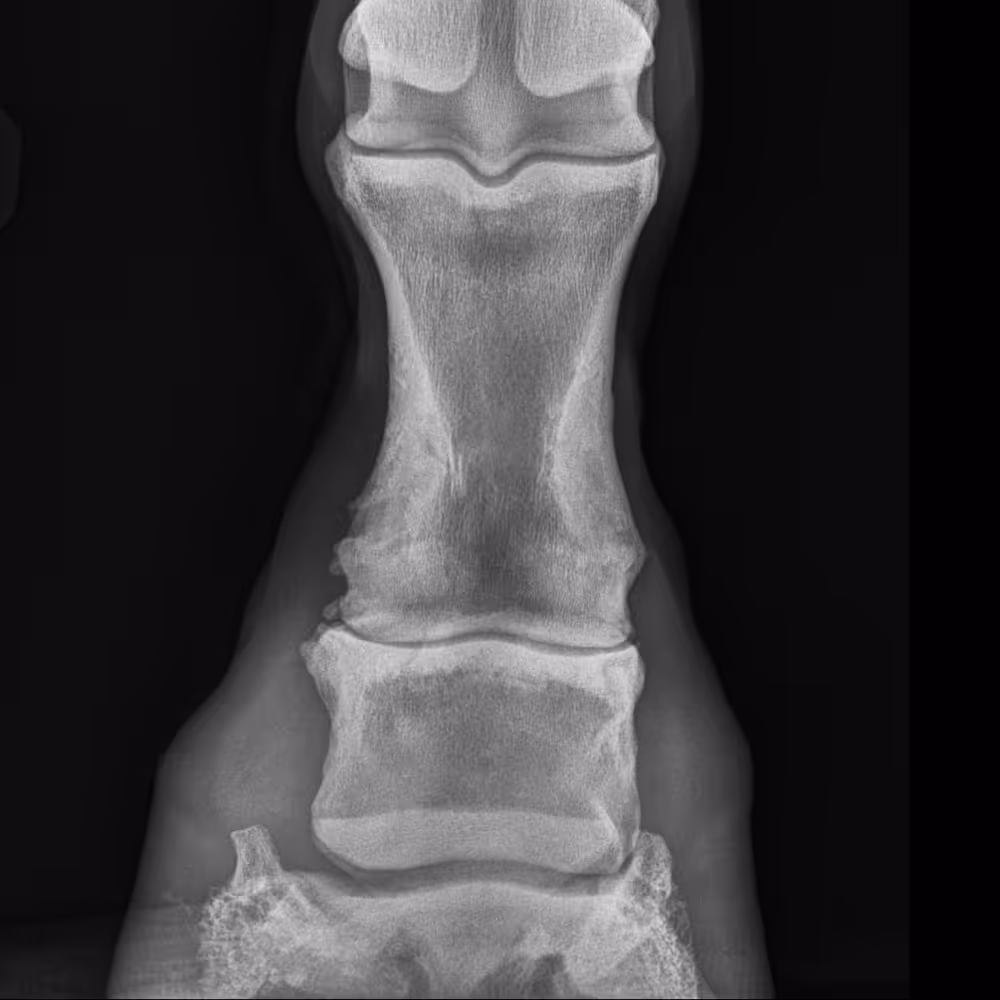

Severe OA of the proximal interphalangeal joint, with new bone proliferation dorsally and laterally, and joint space narrowing laterally.

X-ray image

Severe OA of the distal and proximal interphalangeal joints, with loss of definition of dorsal joint margins due to osteophyte formation and bone remodeling.